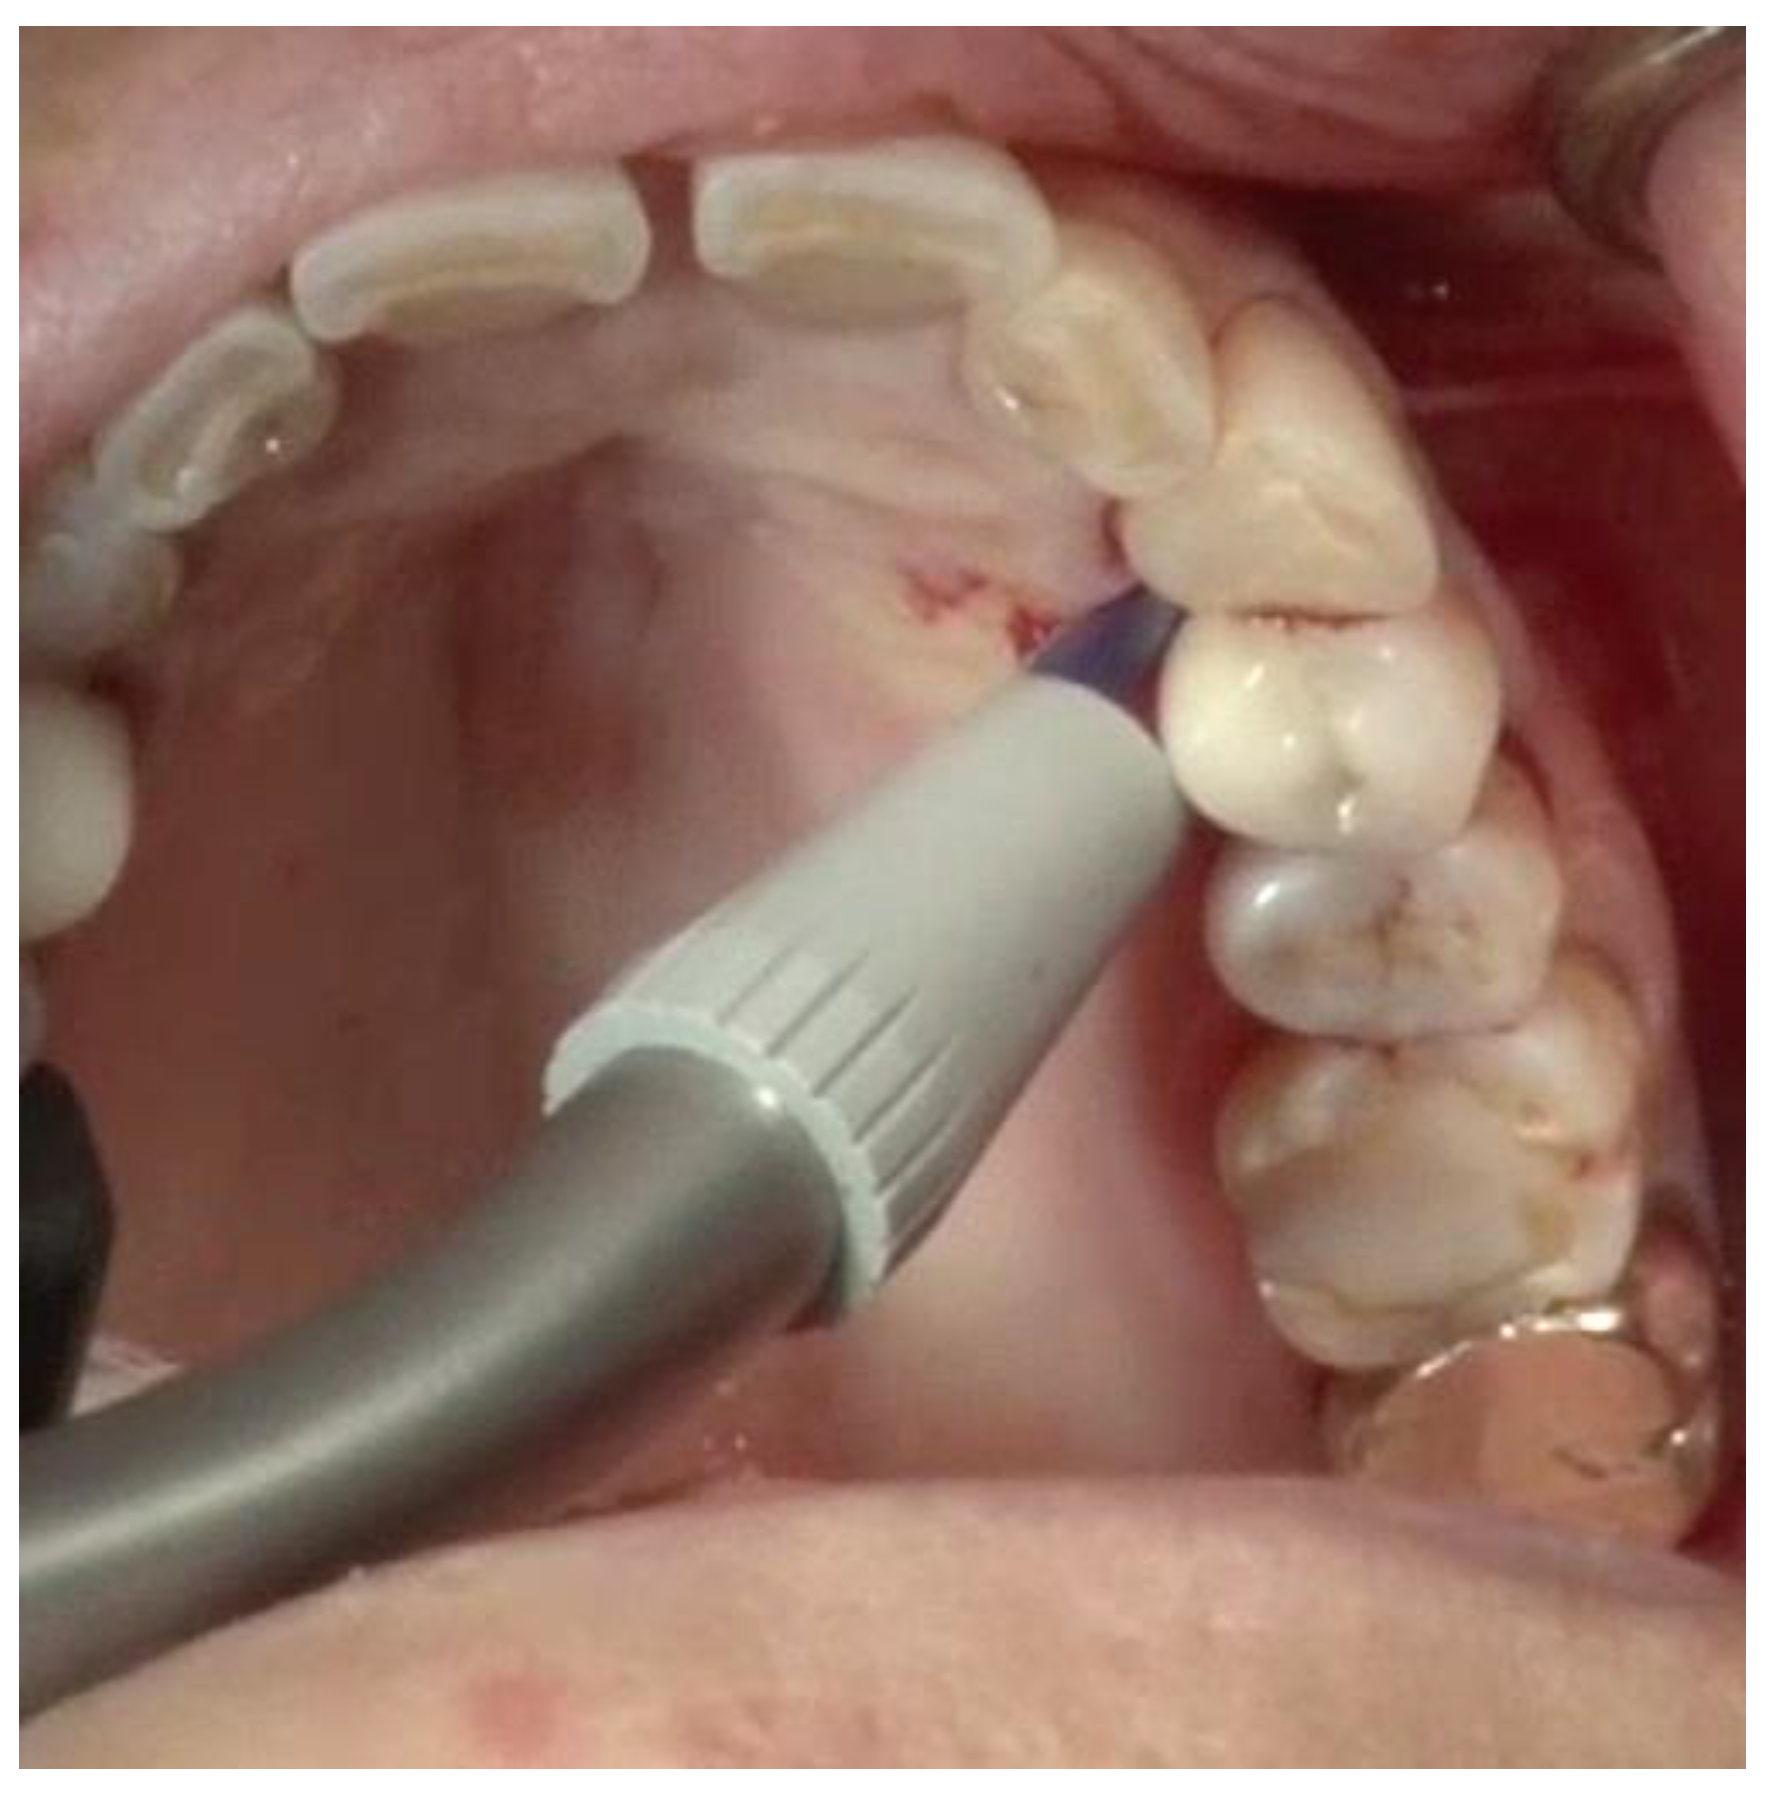

Debridement—Once incisions and the small split-thickness lingual flap have been made, the retractor on the handpiece of the videoscope is inserted, and light pressure is placed on the flap so that the defect can be visualized. Generally, there will be a significant amount of granulation tissue in the defect which must be removed. This is usually performed with a Younger-Goode curette that has been reduced in size by about one-third from its original size. This curette is used in an action similar to using an instrument to “spoon” out caries from a tooth. This action is more suitable for the small flaps of VMIS than the traditional “scaling” action used with surgical curettes. Once the granulation tissue has been removed, the root surfaces can be debrided of accretions and roughness. This is performed with a combination of ultrasonic instrumentation and hand instruments. The videoscope is used throughout the debridement process. When an ultrasonic scaler is used, there will be some transient blurring of the videoscope image due to water on the lens, but the air over the lens clears the image in a matter of seconds when the ultrasonic scaler is turned off. After mechanical debridement of the roots, they are dried with gauze and thoroughly inspected with the videoscope. The 20 to 40× magnification of the videoscope often reveals “micro-islands” of calculus and anatomical roughness on the root surface. 20 These can be removed with the use of EDTA (Prefgel, Straumann, USA), recommended by the manufacturer for the biomodification of the root surface before using EMD. A fully debrided defect ready for bone grafting is shown in Figure 4.

The existing literature on minimally invasive periodontal surgery, the literature on the videoscope, the literature on VMIS, and the techniques designed around the advantages of the videoscope have been reviewed. The published clinical results are favorable and indicate that VMIS can be used to consistently regenerate bone around periodontally damaged teeth with no recession and a possible improvement in soft tissue height. In addition, the application of the VMIS technique to peri-implant bone loss has been reviewed. The videoscope is also being used for other surgical and non-surgical procedures. Some of these are surgical and non-surgical endodontic procedures (Figure 10), sinus elevation surgery (Figure 11), and non-surgical hygiene procedures. Research in these applications is ongoing.